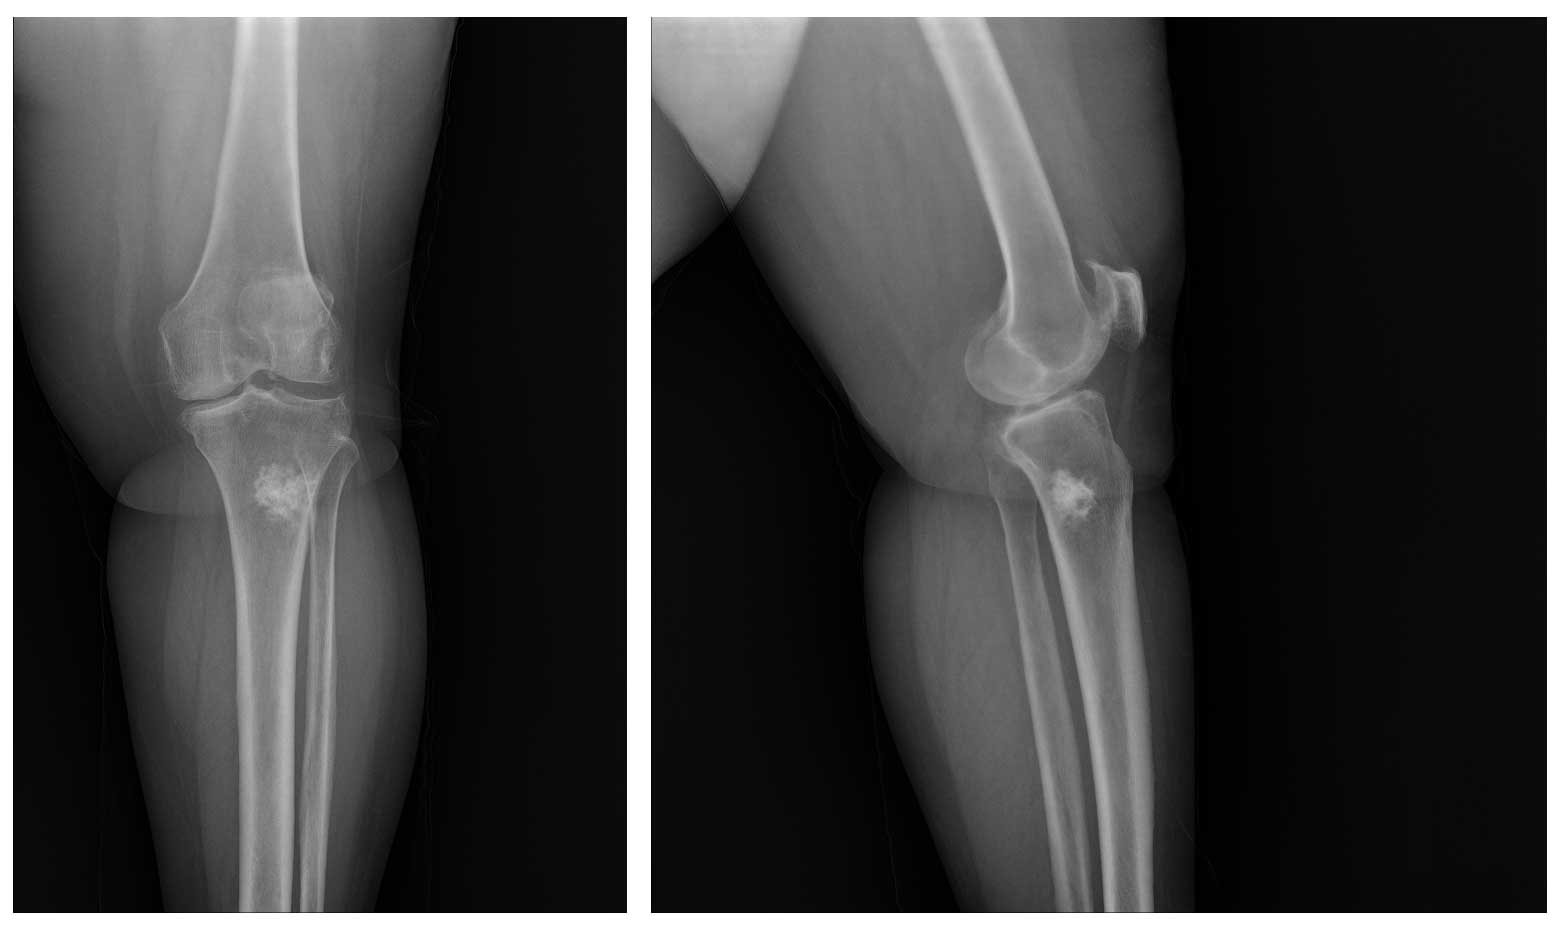

Ameliyat Öncesi: Röntgende proksimal tibia lateralde düzensiz sınırlı sklerotik kitle görülmekte.